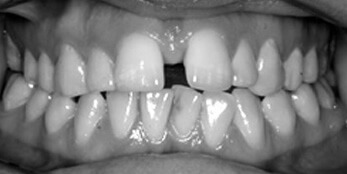

See the smiles we have transformed